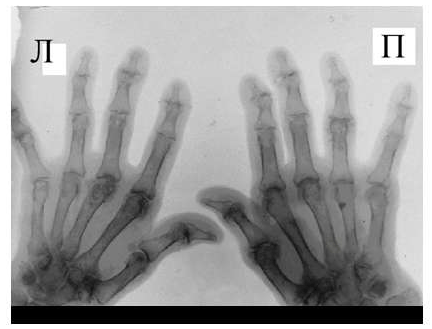

Умеренно выраженные или крупные остеофиты, деформация краев суставных поверхностей, значительное сужение суставных щелей, остеосклероз (узелки Гебердена в дистальных межфаланговых суставах и узелки Бушара в проксимальных), кисты со склеротическим ободком, краевые дефекты суставных поверхностей, при этом костные выступы с одной стороны могут вклиниваться в другую. Обычно краевые дефекты окружены зоной остеосклероза (рис. 3).

Рис. 3. Обзорная Rо-графия кистей.

Множественные артрозы дистальных и проксимальных межфаланговых суставов. Множественные узелки Гебердена и Бушара. Выраженный артроз 1-го левого запястнопястного сустава